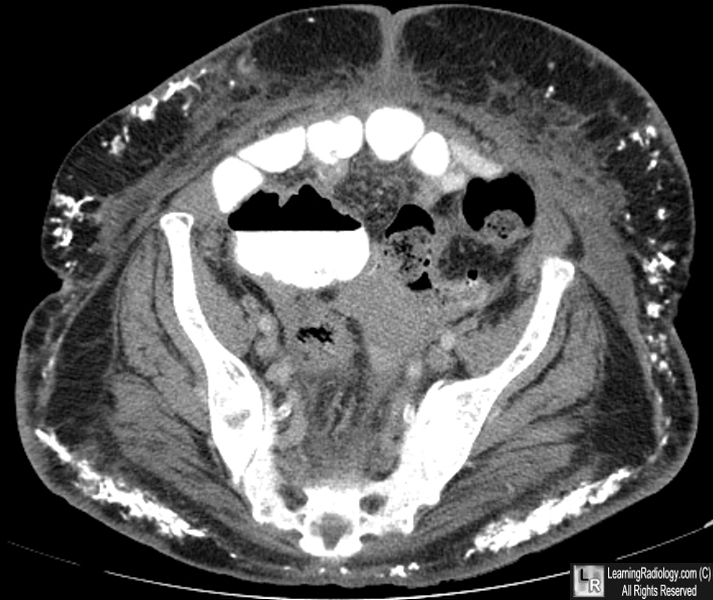

dermatomyositis. soft tissue calcs without raging arthritis

dermatomyositis

soft tissue calcs, specifically intramuscular. Weakness

polymyositis, dermatomyositis

Soft tissue calcs (most commonly intramuscular)

Polymyositis and dermatomyositis